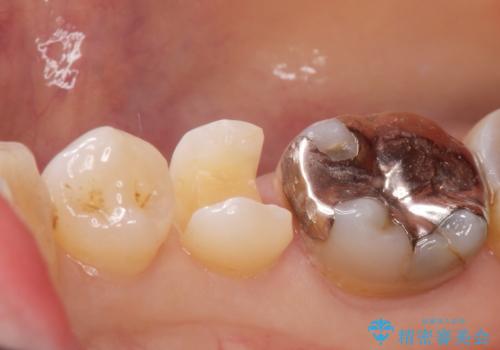

- 口を開けると銀歯が見えるのが嫌とのことで来院。

銀歯を外し、拡大鏡下で虫歯を全て取り除き、白い詰め物(e-maxインレー)にて治療することになりました。

まずは一つ治療したいとの事だったので手前の小臼歯から行いました。